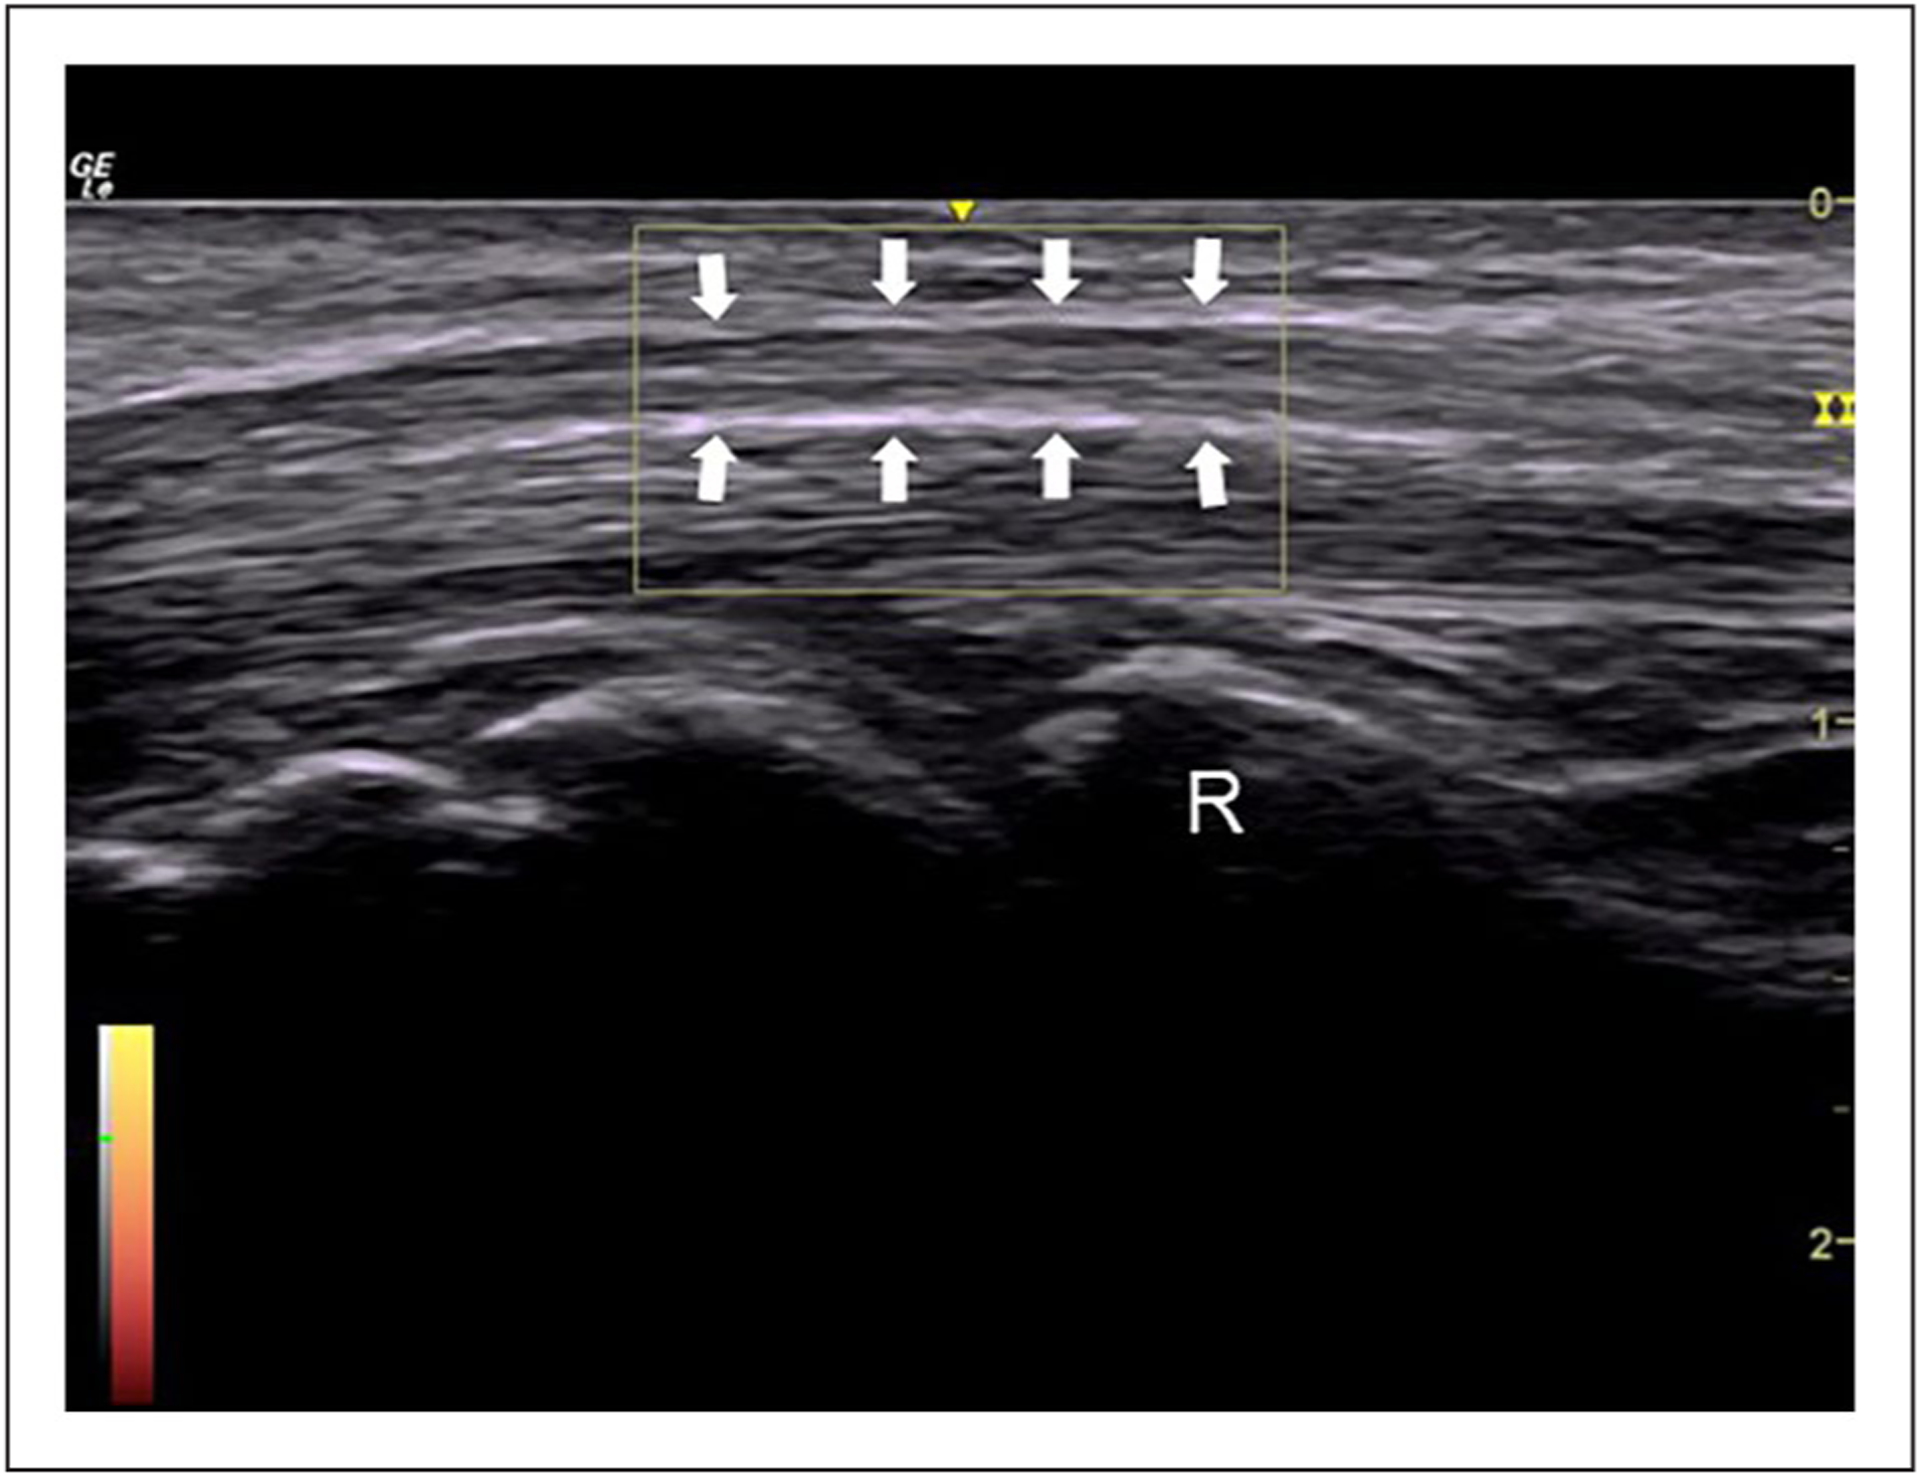

This study examined the implementation of a Doppler sonography imaging protocol to assess intraneural blood flow, within the median nerve, in healthy individuals.

A large percentage of missing evidence (11%–35%) across proximal, mid, and distal carpal tunnel locations. Only a quarter of cases with evidence of intraneural blood flow had the strongest evidence of a power Doppler video clip, of which only three-quarters were valid. The study identified potential areas for improving the imaging protocol to reduce missing data and improve data quality.

This study demonstrates the significance of a standardized imaging protocol to guide the sonographic acquisition of Doppler images and provides important insights into potential issues with data quality. The recommendations have the potential to help future studies assess intraneural blood flow in healthy populations in a more rigorous and reliable way. Incorporating the study’s recommendations into a standardized protocol, there is potential to enhance the diagnostic accuracy of carpal tunnel syndrome and improve diagnosis and treatment.